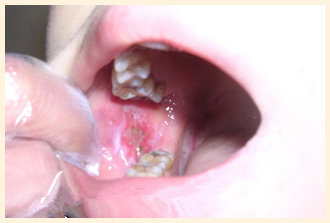

患者陈某,女,60岁,广东省深圳市人,患口腔扁平苔藓,自述口腔扁平苔藓多年,多方反复治疗无效,故来我院就诊。检查:右颊粘膜大面积红,表面有许多网状白膜。左颊大面积粘膜红,下部一块红溃烂,表面有白膜。经治疗10天红已减轻,经治疗4个疗程,双颊红溃已消除,但是表面还有少许白膜,经治疗第5个疗程时,白膜已消除,基本恢复正常。

陈某治疗前

陈某治疗后